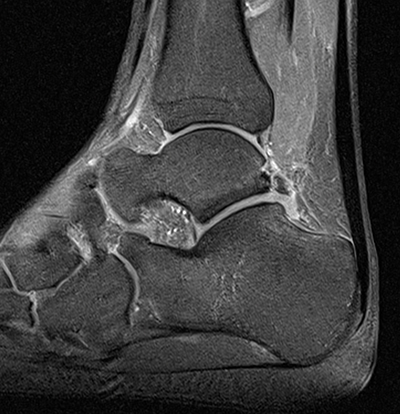

MRT

Die Kernspintomographie hat ihre Stärke in der Darstellung von Weichteilverletzungen. Insbesondere Verletzungen der Wachstumsfuge, des Periosts und der Bänder lassen sich gut visualisieren. Nachteilig ist die Untersuchungsdauer von 20-30 Minuten. Bleibt das Kind während dieser Zeit nicht ruhig liegen, kommt es zu Bewegungsartefakten, welche die Beurteilbarkeit der Bilder beeinträchtigen.

Osteochondrale Verletzungen können infolge eines Distorsionstraumas beobachtet werden (Taluskantenfraktur), teilweise lässt sich auch kein Trauma eruieren. Der es sich bei osteochondralen Verletzungen um keine Arthrose handelt, ist gerade bei Schmerzfreiheit ein defensives Vorgehen angezeigt. Bei offenen Wachstumsfugen kann eine osteochondrale Verletzung unter konservativer Therapie ausheilen.

Eine retrograde Anbohrung ist indiziert, wenn sich im MRT Verlauf eine zunehmende Sklerosierung im Randbereich der Läsion zeigt bei intakter Knorpeloberfläche.

Instabile Knorpelareale werden arthroskopisch entfernt in Verbindung mit einer Mikrofrakturierung der subchondralen Knochenlamelle.